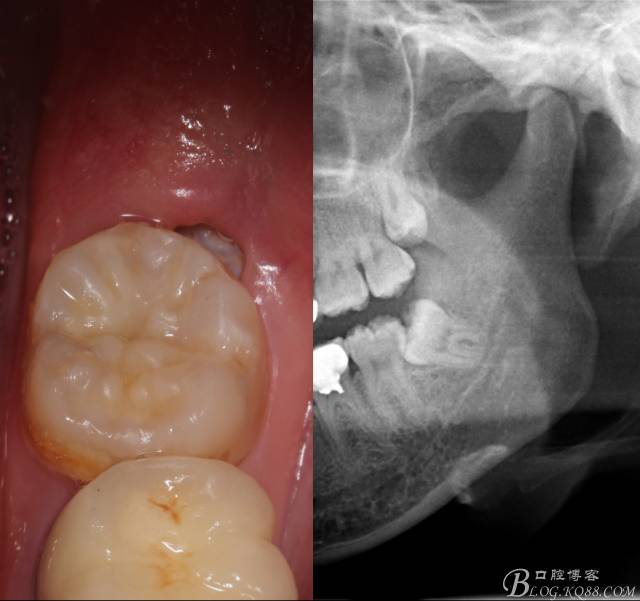

補(bǔ)完牙后,準(zhǔn)備撥除阻生智齒了。

先分析智齒的情況,口內(nèi)直觀是半個(gè)牙尖都沒(méi)露出來(lái),差一點(diǎn)就完全埋伏了。磨牙后墊的可操作面積中規(guī)中紀(jì),X全景片示三類阻生,根冠比例是1:1,非融合根,近中根壓下頜管。